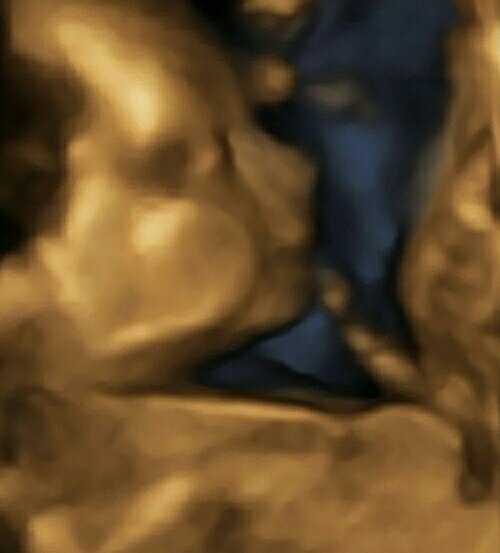

Kochane tutaj kilka fotek z 3d .

1 PINDOR ( patrzac po rozmiarze to chyba bedzie do kolan [emoji23][emoji23][emoji23])

1472716983210.jpg